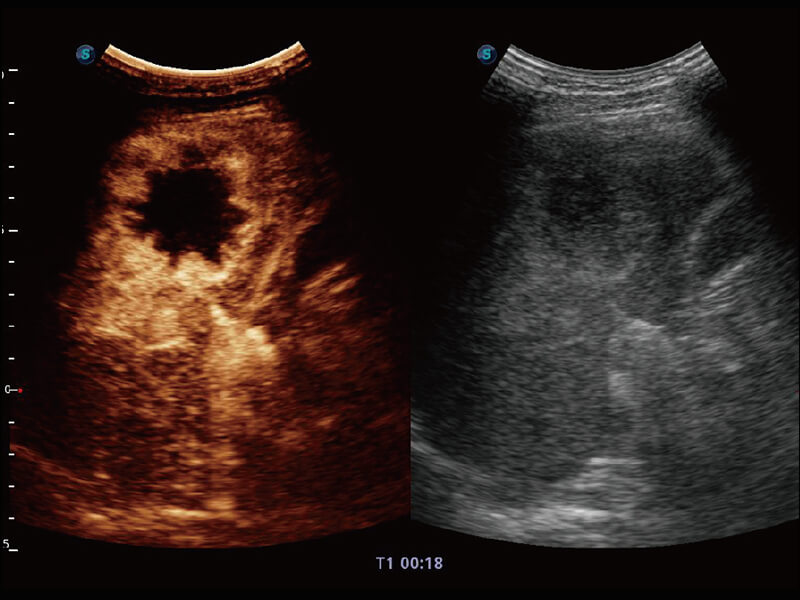

S60探头工艺,从前端信号处理每一个环节采集无损声学数据,真实还原组织原貌,再现解剖细节。

高分辨率容积成像 栩栩如生

超宽频带技术,为容积成像带来优质的二维图像基础,为您呈现丰富的结构细节,栩栩如生地展示宝宝的宫内形态以及各种组织的立体结构。